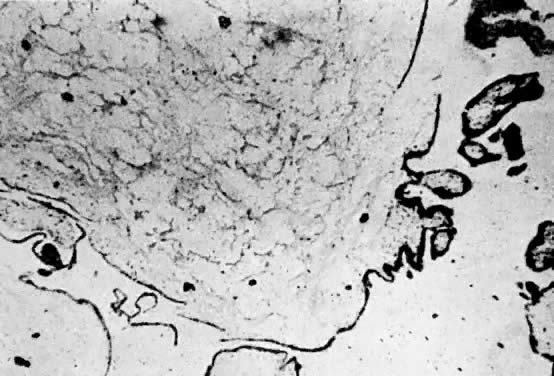

Gestational Choriocarcinoma

Choriocarcinoma is characterized by a dimorphic population of cytotrophoblast and syncytiotrophoblast elements (Fig. 9 and Fig. 10).35 Varying amounts of pleomorphism and anaplasia are present; in the absence of clinical history, the histopathology may be misinterpreted in biopsy specimens of metastatic sites as undifferentiated carcinoma or sarcoma. Chorionic villi are not present, even in primary uterine sites of disease. If villous structures are identified in metastatic deposits, the histologic diagnosis is invasive mole.

Fig. 9. Uterus removed for choriocarcinoma. The extensive necrosis, vascular penetration, and hemorrhage are evident from this specimen.

Fig. 10. Microscopic view of choriocarcinoma taken from the uterus illustrated in Figure 9. Sheets of anaplastic trophoblastic cells are noted without the maintenance of the pattern of the villi. Extensive necrosis is evident.

Gestational choriocarcinoma, similar to other forms of normal and abnormal trophoblast, readily invades into blood vessels, producing metastasis through hematogenous routes of dissemination. The embolic metastatic sites have a tendency to rapidly outgrow their blood supply, producing central necrosis, which can result in massive local hemorrhage.35 Secretion of hCG is retained by the vast majority of gestational choriocarcinomas, because the tumor is derived from elements of both cytotrophoblast and syncytiotrophoblast.35 This tumor marker correlates well with the volume of disease except in a few cases of drug-resistant disease and is a sensitive marker for response to chemotherapy.35 Gestational choriocarcinoma usually progresses rapidly and is fatal without treatment.